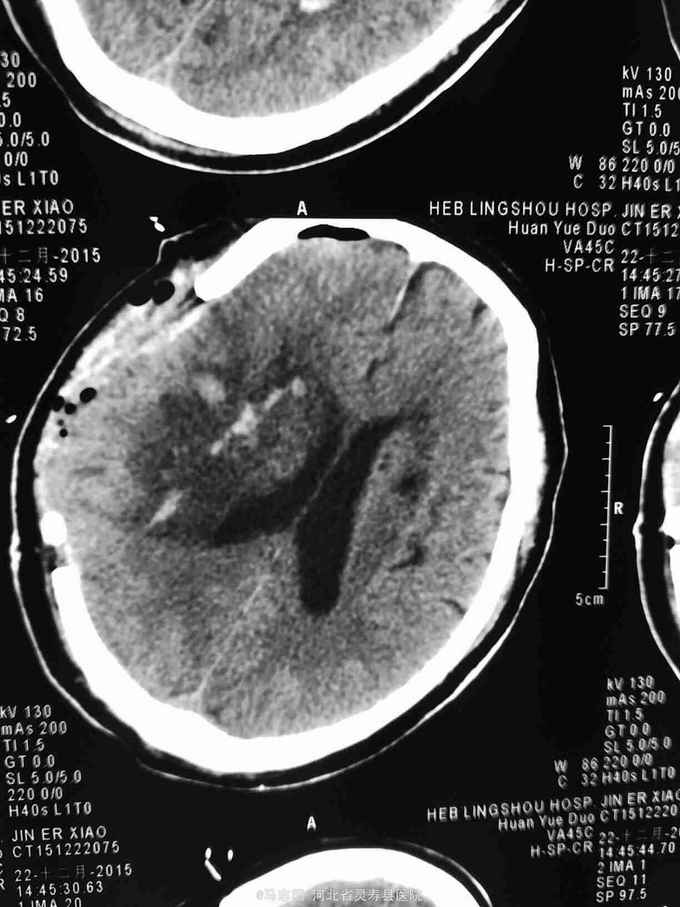

1.右侧基底节脑出血并脑疝形成2.高血压3级 极高危。急诊行血肿清除,去骨瓣减压术。术后给予降颅压,促醒保护脑神经等治疗。术后第二天复查CT如下